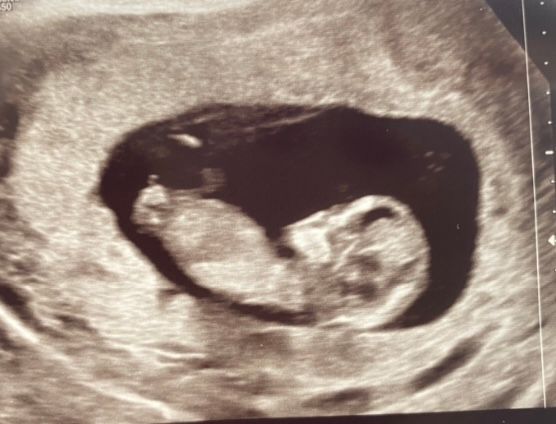

Во вторник 19.07. на узи обнаружилось, что не бьется сердце малышки. Срок был 24 недели и 3 дня.

если кратко: пришлось вызывать роды, пережить схватки и родить мертвую девочку.

если кратко: пришлось вызывать роды и родить мертвую девочку.